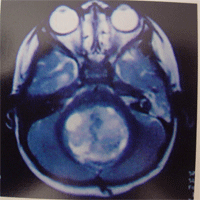

1.頭顱X線平片 頭顱X線可見有顱縫增寬等顱內高壓征,腫瘤鈣化極為罕見。2.CT 可見小腦蚓部或四室內均勻一致的等密度或稍高密度占位,多與四腦室底有分界,將腦幹向前推移。腫瘤周邊環繞有薄的低密度水腫帶明顯均勻強化腫瘤鈣化囊變少見。典型髓母細胞瘤一般直徑大於3.5cm,位於後顱凹中線之小腦蚓部累及上蚓部的腫瘤延伸到小腦幕切跡之上在頭顱CT上87%呈現為均勻一致的高密度影10%為等密度病灶,病灶中有小壞死時平掃亦可呈不均勻之混雜密度少數有鈣化,偶可呈低密度囊性變病灶邊界均較清晰多位於小腦蚓部,成人患者可多見於小腦半球增強檢查呈均勻一致的強化。有時病灶周圍環繞有一條薄的低密度水腫帶第四腦室常被推移向前,可伴有梗阻性腦積水征。當出現腦室室管膜下轉移時,可在腦室周邊出現完全或不完全略高密度影像,成帶狀,可有明顯強化。與室管膜瘤的鑑別主要是髓母細胞瘤的鈣化及囊性變少見,病灶密度比較均勻。3.MRI 腫瘤實質部分表現為長T1長T2信號矢狀位可更好地顯示腫瘤起源於小腦的蚓部及腫瘤與四腦室底的關係見圖2圖3所示,這可視為與室管膜瘤的鑑別點在MRI T1圖像上,腫瘤一般信號強度均勻發生壞死或囊變時,腫瘤內部可見到較腫瘤更長T1、更長T2的病灶區。在T2圖像中67%腫瘤呈高信號,另33%例呈等信號97%瘤周有明顯水腫。由於髓母細胞瘤的實質部分信號強度的特點不甚突出,故腫瘤所在部位及由此而產生的間接徵象則顯得較為重要,可了解與腦幹之間關係,因此正中矢狀掃描圖像尤為關鍵,冠狀掃描可作為三維影像參考在MRI矢狀點陣圖像上74%可見腫瘤與第四腦室底間有一極細長的低信號分隔帶與室管膜瘤不同髓母細胞瘤很少向第四腦室側隱窩及橋小腦角伸展。少數患者MRI可見腫瘤沿蛛網膜下腔轉移,顯示小腦葉的邊界模糊,MRI矢狀位或冠狀位掃描更有價值同時種植病灶亦可被Gd-DTPA顯著增強。97.5%伴有中至重度腦積水。髓母細胞瘤Gd-DTPA增強掃描,腫瘤的實質部分呈顯著異常增強而囊變或壞死區在非延遲掃描狀態下不表現增強。髓母細胞瘤很少有囊性變,腫物位於上蚓部可經小腦幕切跡孔伸入松果體區。

位於小腦上蚓部的腫瘤常使中腦導水管受壓前移或變窄位於第四腦室頂部的腫瘤,四疊體板、前髓帆由原來正常時的直立位置變為近乎水平位導水管擴張且上移髓母細胞瘤可在T1像顯示腫瘤的前方和(或)上方在瘤體周邊新月形的腦脊液殘留影,系沒有被腫瘤完全占據的第四腦室剩餘部分。